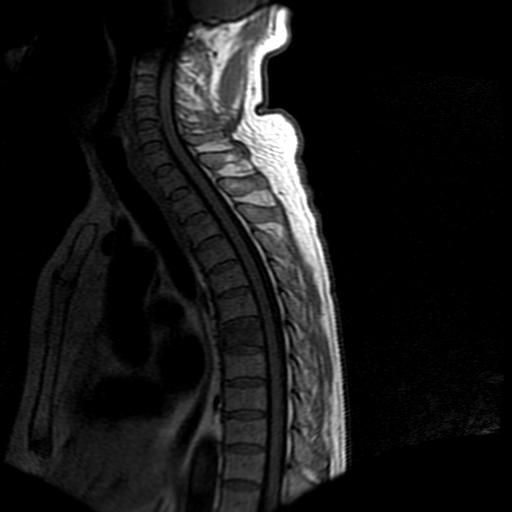

68岁男性,胸部疼痛,不适。

t7椎体前1/3信号略减低,椎体上下面凹陷,相应脊髓几周边软组织信号未见改变。考虑:椎体退变。

陈旧性压缩性骨折

胸7椎体楔状变形及信号异常,附件未见明显异常信号.椎间隙正常.未见软组织块影.考虑骨质疏松所致压缩性骨折可能大.

胸7椎体楔状变形及信号异常[t1t2 均为低信号],附件未见明显异常信号.椎间隙正常.未见软组织块影.考虑陈旧性压缩性骨折伴退变。

首先需除外单发成骨性转移瘤可能。

转移瘤也不能排除